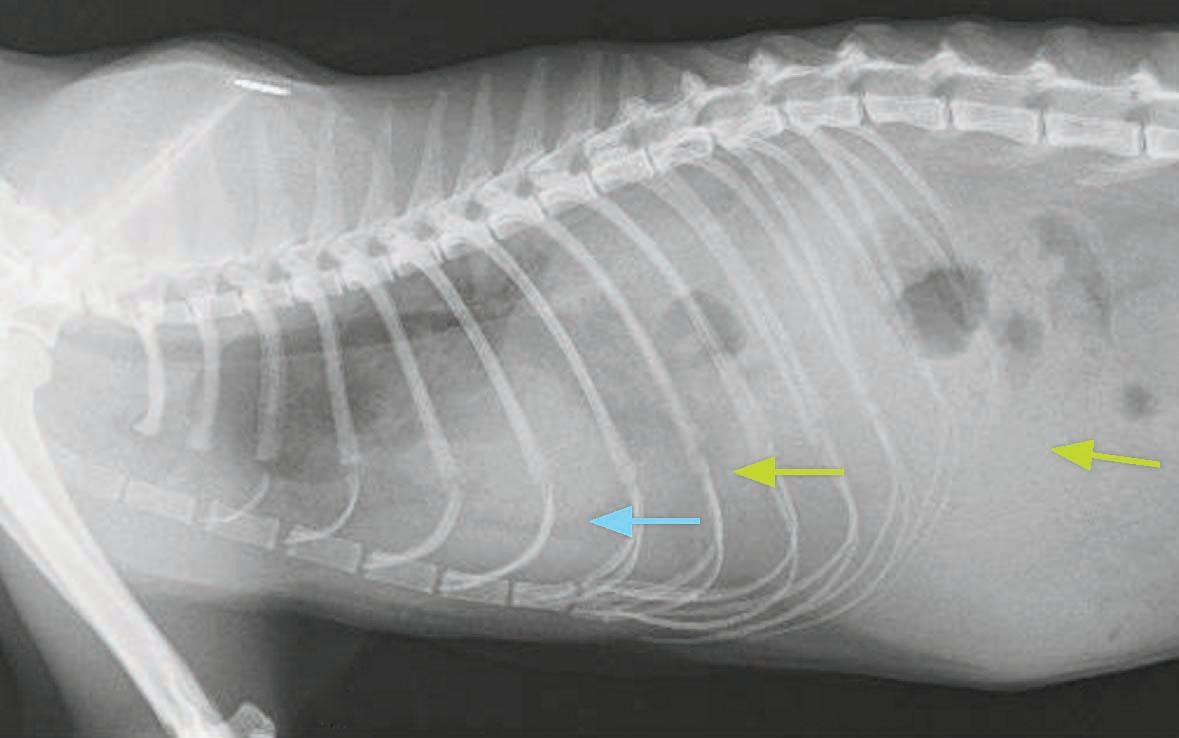

X Ray Diaphragmatic Hernia Cat Side Stock Photo 1660991782 Shutterstock Diaphragmatic Hernia In Cats Symptoms Abnormal breathing posture with extended head and neck. Symptoms of diaphragmatic hernia in cats depend on the severity and cause of the hernia. A diaphragmatic hernia is a condition in which a break in the diaphragm allows protrusion of abdominal organs into the chest. Some of the most common symptoms include: A diaphragmatic hernia produces a range of symptoms in. Diaphragmatic Hernia In Cats Symptoms.